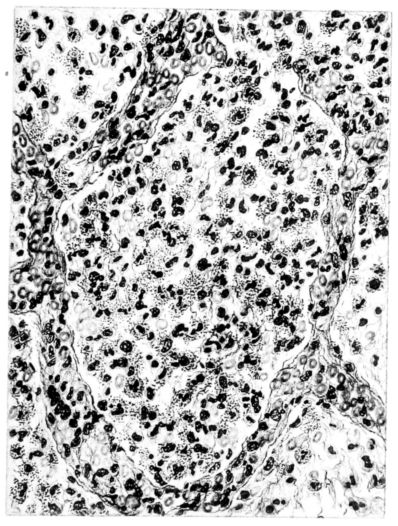

FIG. IV. AUTOPSY NO. 205. CONGESTION AND EDEMA OF THE SUBMUCOSA AND REGENERATION OF THE TRACHEAL EPITHELIUM.

The changes are less marked, perhaps, in the trachea than in its finer ramifications. The mucosa is constantly more or less destroyed and large areas, usually focal, are entirely devoid of their epithelial covering. This is replaced by a sparse exudate, composed largely of red blood cells, mucus, a small amount of fibrin, and nuclear fragments (Fig. II). It may dip into the submucosa for a short distance, but usually these indentures are associated with the ducts of the mucous glands into which the inflammatory reaction extends. A more striking feature than the exudate, however, is the edema and the congestion of the submucosa. The loose areolar tissue of the submucosa is spread widely apart, and throughout it distended blood vessels are very conspicuous. Occasionally such a vessel is broken and actual hemorrhage appears in the submucosa. Occasionally, too, the inflammation extends down the duct to the mucous gland itself, and here, also, aplastic inflammatory reaction is evident, inasmuch as the acini now stain intensely red with the cells undifferentiated from each other and specked here and there by broken remains of the dead nuclei (Fig. III). After the disease has continued for a short period, even at the end of five or six days, some regeneration of the epithelial lining may be seen (3) (Fig. IV). But despite this, the acute picture persists, and there goes on, side by side, an attempted repair characterized by epithelial regeneration and the same evidence of acute change. Since the lesion is essentially a superficial one, scars or contractures of any extent are not encountered in the trachea, even in examples of the disease that have ended fatally only after many weeks.[4]